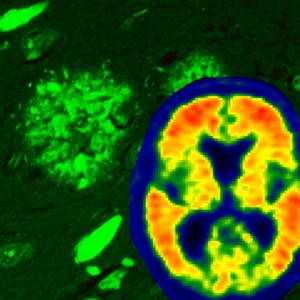

Alzheimer's disease brain pathology is illustrated using thioflavin-S fluorescent microscopy, which reveals both neurofibrillary tangles (flame-shaped structures) and amyloid plaque pathology (rounded structures). Through the use of the amyloid brain scanning, we are now able to visualize amyloid accumulation in the brains of living individuals – visualized with warmer colors. Credit: Mayo Clinic

"Amyloid, on the other hand, starts accumulating in the outer parts of the cortex and then spreads down to the hippocampus and eventually to other areas," she says. "Our study shows that the accumulation of amyloid has a strong relationship with a decline in cognition. When you account for the severity of tau pathology, however, the relationship between amyloid and cognition disappears -- which indicates tau is the driver of Alzheimer's," Dr. Murray says.

The investigators found that the signal from amyloid brain scans corresponded with amyloid pathology specific to the brain and not amyloid found in vessels, and did not correspond to tau pathology. The brains of some participants had amyloid visible at pathology that did not reach the threshold for what would be found in Alzheimer's brain scans. This is important, as amyloid can be found in brains of older individuals who have not experienced cognitive decline, researchers say.